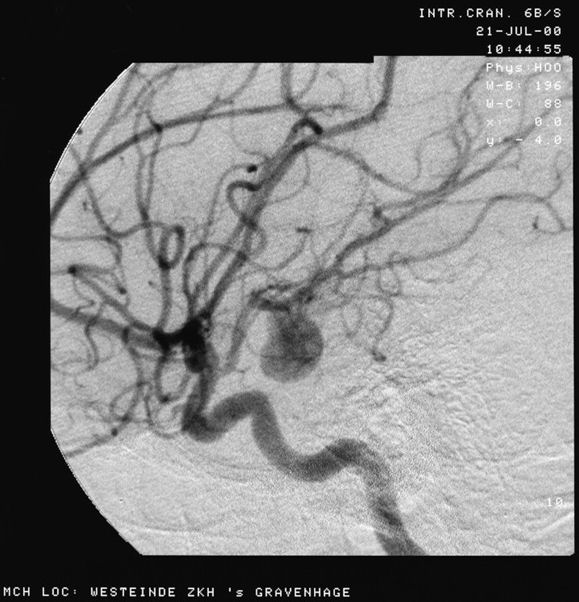

Source: Aneurysem.jpg

Date: 21 Julie 2000

Author: Lucien Monfils